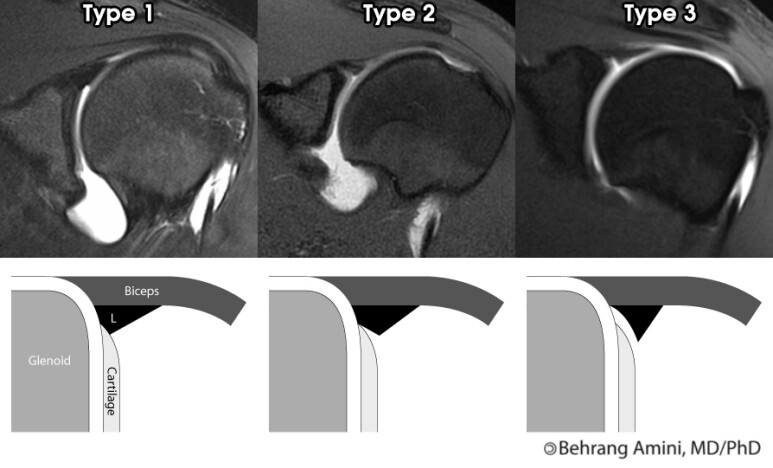

▶ SLAP lesion 4type

- 제1형 : 관절와순은 관절와에 부착되어 있으나 마모 및 변성이 있는경우(이두장건 부착부는 분리되지 않은 상태)

- 제2형(가장 흔한 유형) : 관절와순 및 이두장건의 박리가 있는경우(이두장건 부착부위가 파열되어 일부 분리)

- 제3형 : 양동이 손잡이 파열로서, 상부관절와순이 파열되어 관절안으로 전위되었으나 이두장건 부착부위는 손상이 없는경우

- 제4형 : 상부관절와순의 파열이 이두장건까지 연장되어 있으며 관절안으로 전위되어있는경우로서 드문 유형입니다.